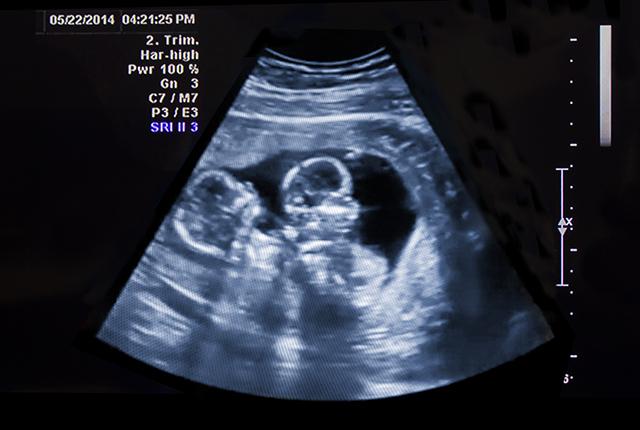

A study of 84 twin/sibling pairs exposed to alcohol in utero shows that two fetuses exposed to identical levels of alcohol can experience strikingly different levels of neurological damage. Risk of damage does not depend solely on the pregnant woman's alcohol consumption; rather, fetal genetics plays a vital role, according to findings published today in the journal Advances in Pediatric Research.

In the study, UW Medicine researchers with the Fetal Alcohol Syndrome Diagnostic & Prevention Network analyzed data that had been gathered over more than 26 years. They found that when twins with identical DNA experienced identical alcohol exposure, the fetal alcohol outcomes were identical. In contrast, among genetically non-identical twin pairs with identical alcohol exposures, their fetal alcohol outcomes often differed, sometimes strikingly: one could be born with severe fetal alcohol syndrome (FAS) and the other only mildly affected.

Of the 84 pairs, there were nine identical twins, 39 fraternal twin pairs, 27 full sibling pairs and 9 half-sibling pairs. Genetic relatedness – the amount of DNA shared between sibling pairs –is 100 percent between identical twins-pairs, 50 percent between fraternal twin pairs, 50 percent between full-sibling pairs and 25 percent between half-sibling pairs that share a common birth mother. As genetic relatedness decreased across the four groups, the proportion of sibling pairs with different fetal alcohol outcomes increased from zero to 44 percent to 59 percent to 78 percent, respectively.